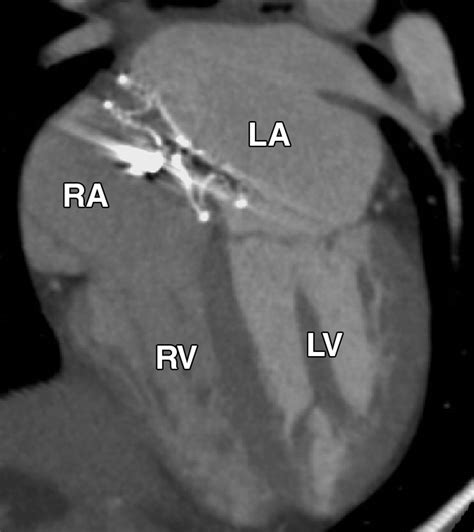

The Amplatzer Septal Occluder is specifically designed to address this by sealing the defect. It is essentially a self-expanding, double-disk device made from a flexible nitinol wire mesh. Once placed, it creates a "sandwich" effect that covers both sides of the hole, allowing the patient's own tissue to grow over the device over time, effectively healing the septal wall.

• Deployment: The Amplatzer Septal Occluder is pushed through the catheter. The left atrial disk is deployed first to anchor the device, followed by the right atrial disk.

Safety is the cornerstone of this medical device. The nitinol mesh used is biocompatible, meaning the body is highly unlikely to reject it. Furthermore, the device is designed to be retrievable before full deployment if the cardiologist determines that the positioning is not optimal, adding an extra layer of clinical safety to the procedure.